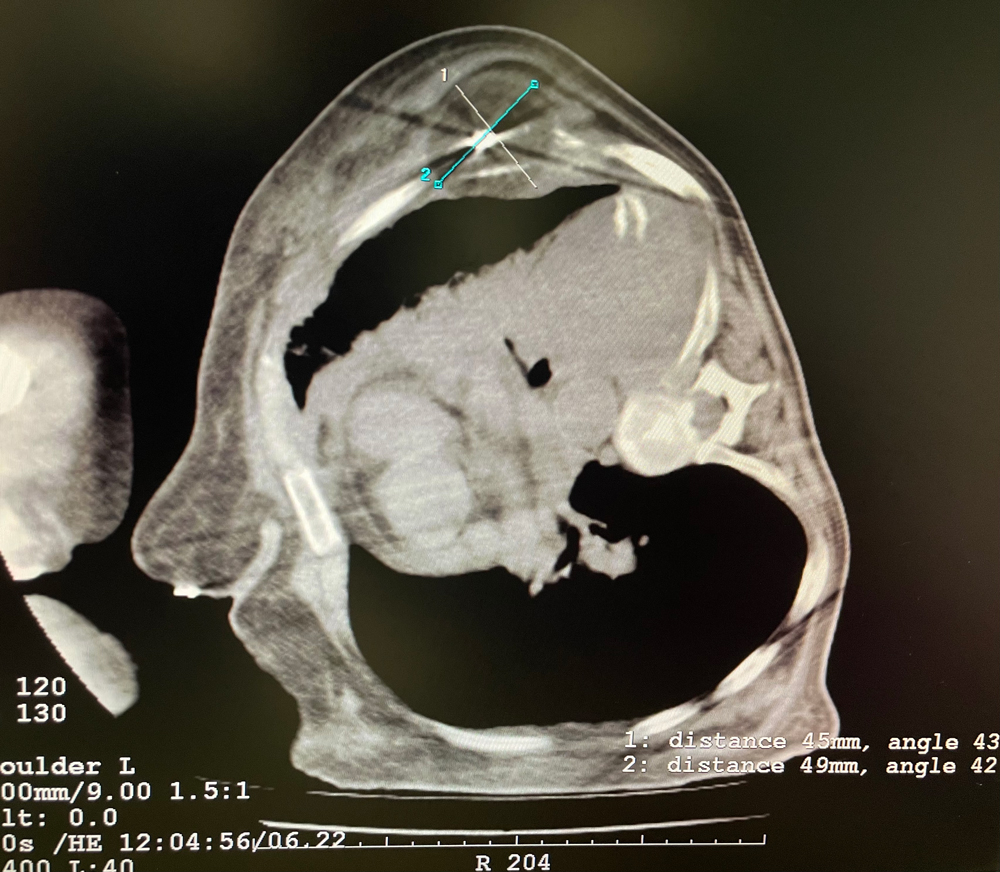

患者一

女,56岁,肺转移瘤,骶骨、左侧肋骨各一转移灶,病灶大小均为5cm。骶骨转移灶、肋骨转移灶各进行2个冻融循环。患者术后状况良好。